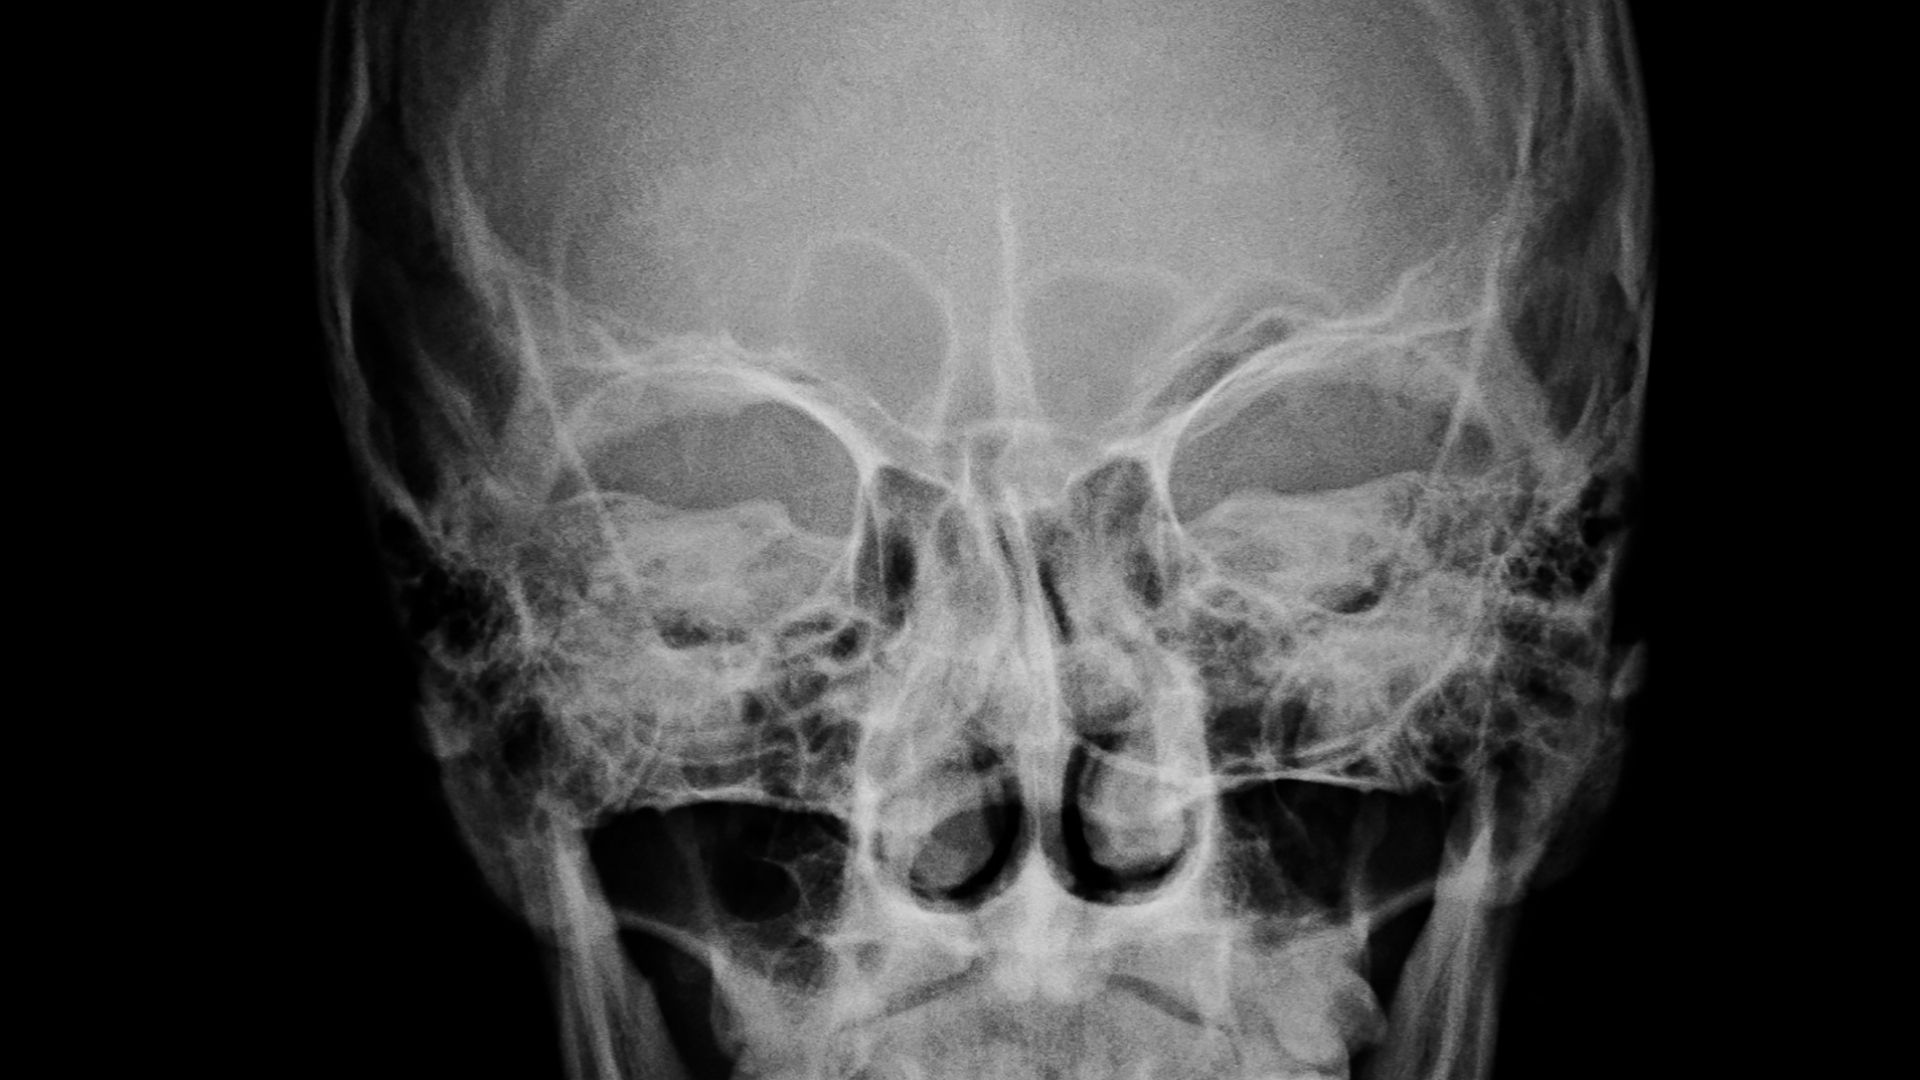

Chụp X-quang đầu là kỹ thuật chẩn đoán hình ảnh sử dụng tia X để ghi lại hình ảnh các cấu trúc xương vùng đầu, bao gồm xương sọ và một số vùng liên quan. Thông qua hình ảnh thu được, bác sĩ có thể quan sát hình dạng, cấu trúc và phát hiện những bất thường ở xương, từ đó hỗ trợ chẩn đoán ban đầu.

X-quang đầu có giá trị trong việc phát hiện các tổn thương liên quan đến xương sọ. Bác sĩ có thể nhận biết tình trạng nứt, gãy hoặc biến dạng xương sau chấn thương. Trong một số trường hợp, hình ảnh X-quang còn giúp phát hiện dị vật cản quang nằm trong vùng đầu, đặc biệt là sau tai nạn.

Tùy theo mục đích chẩn đoán, bác sĩ có thể chỉ định chụp X-quang đầu ở một hoặc nhiều tư thế khác nhau. Tư thế chụp thẳng giúp đánh giá tổng quan cấu trúc xương sọ và phát hiện các tổn thương rõ rệt. Tư thế chụp nghiêng hỗ trợ quan sát những vùng khó nhìn thấy ở tư thế thẳng, đặc biệt là các khe xương hoặc vùng phía sau đầu.